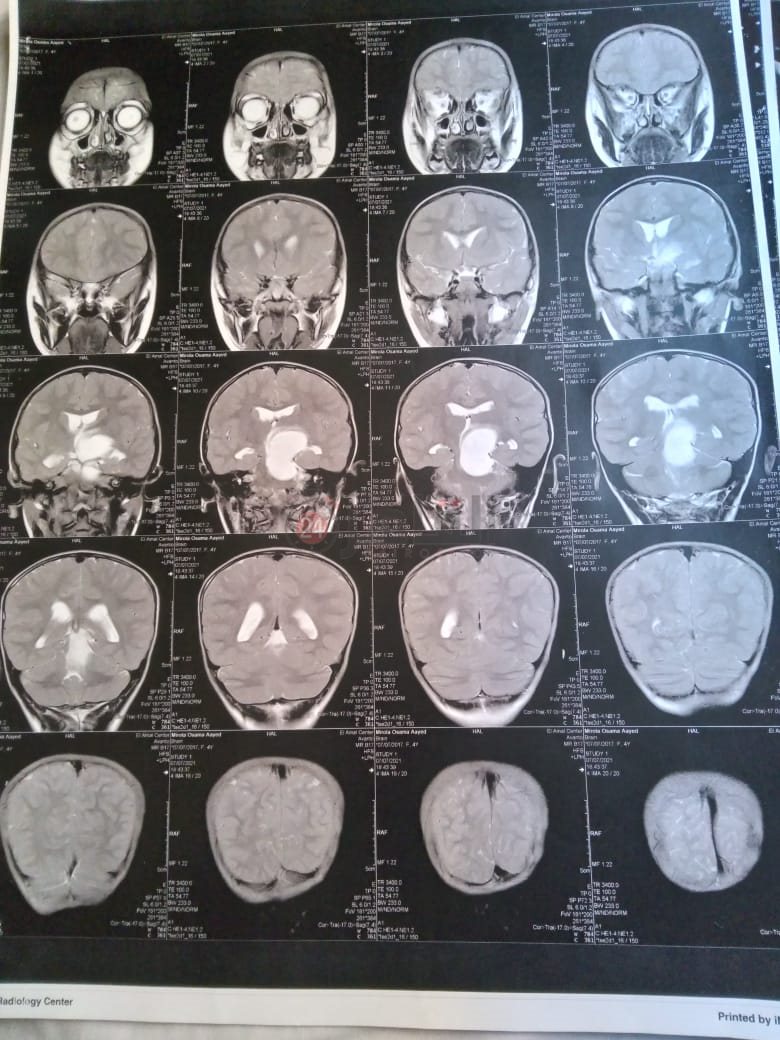

وأضاف: "أجرينا أشعة مقطعية لها لم يظهر بها أي شيء، ثم طلب الطبيب إجراء أشعة رنين على المخ، وهنا تبين وجود بؤرة سرطانية بالمخ، مشيرًا إلى أن:" الدكتور طلب مني أذهب إليه لوحدي من غير الأم والبنت، وقالي إن في ورم بس مش عارفين نوعه خبيث ولا حميد".

وأوضح أن حالة نجلته تتدهور بسرعة كبيرة، حيث أصُيبت حاليًا بشلل نصفي بالجانب الأيمن، لأن البؤرة حجمها 2.5 سم في 4.5 سم، ومرتكزة على جانبها الأيمن، مشددًا على أنها الحالة الأولى في العائلة التي تصاب بهذا المرض.